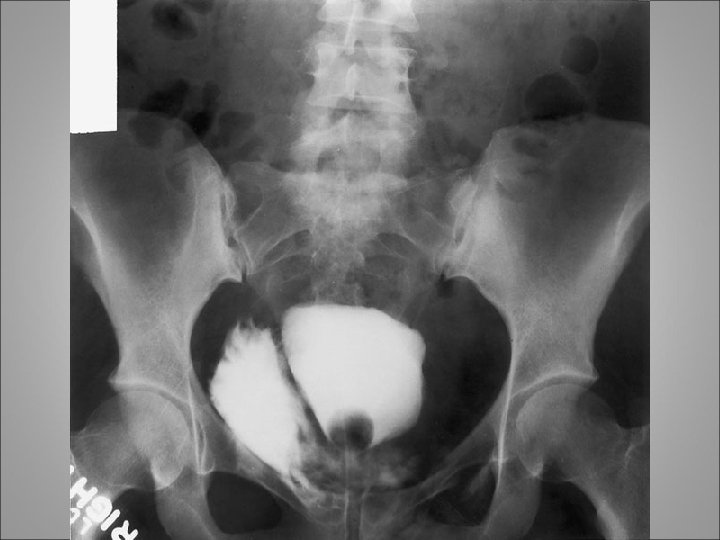

Intra and extra peritoneal bladder rupture

Diagnosis • Symptoms include hematuria or inability to void • Physical examination may reveal blood at the meatus or a high-riding prostate gland upon rectal examination. Extravasation of blood along the fascial planes of the perineum is another indication of injury to the urethra • The diagnosis is made by performance of a retrograde urethrogram • "Pie in the sky" findings revealed by cystogram usually indicate urethral disruption